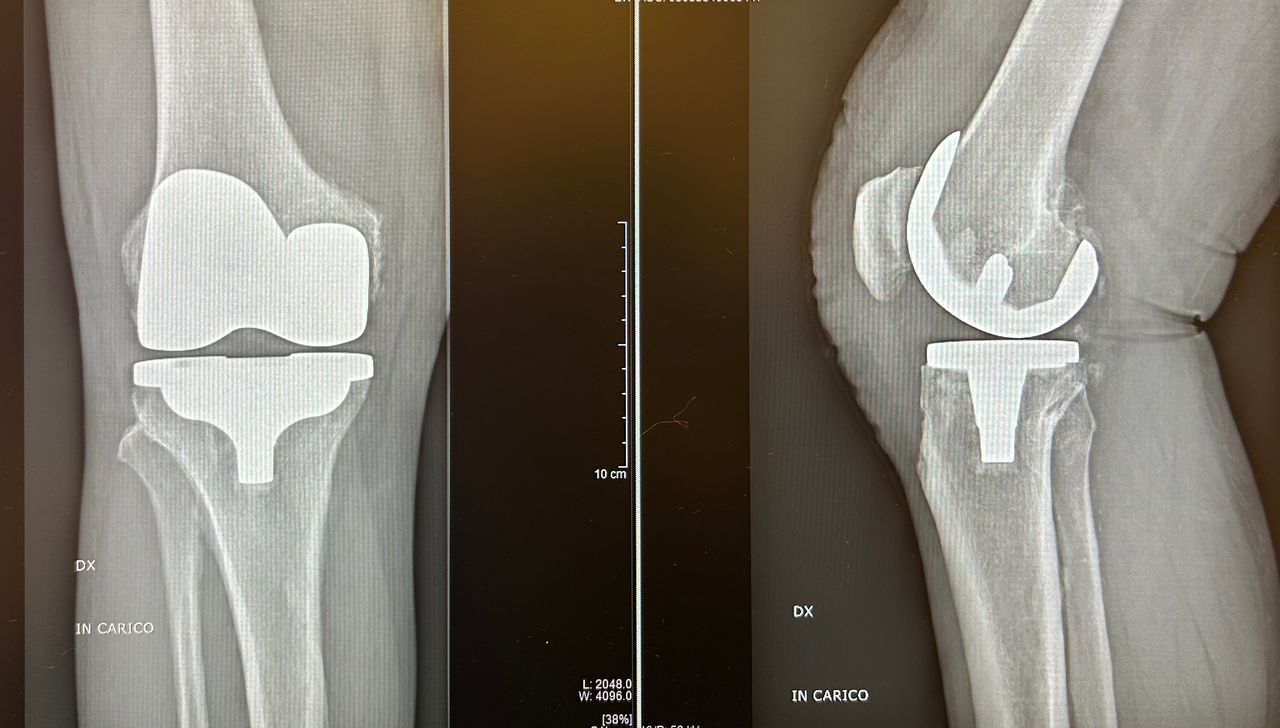

Mi chiamo Luca Luciano e sono un medico ortopedico specializzato nella chirurgia protesica dell’anca e del ginocchio. Da anni mi occupo del trattamento dell’artrosi severa, utilizzando tecniche mini invasive moderne che mi permettono di ridurre il dolore post-operatorio e favorire un recupero più rapido e sereno.

Credo in una chirurgia precisa, attenta e rispettosa dei tessuti. Ogni intervento viene pianificato con cura, valutando la storia clinica, le esigenze e lo stile di vita della persona che ho di fronte. Il mio obiettivo non è solo sostituire un’articolazione consumata, ma restituire qualità di vita, autonomia e sicurezza nei movimenti quotidiani.

• Chirurgia del ginocchio